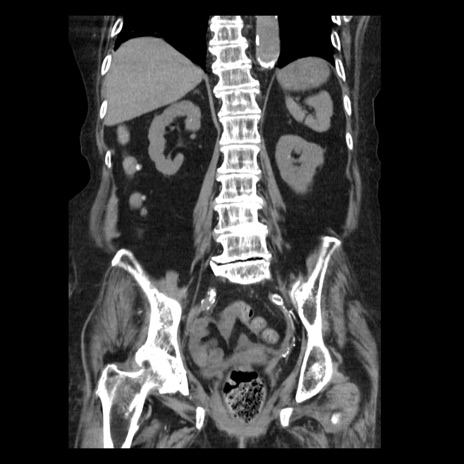

症例14(冠状断像)

【症例】 90歳代女性

【主訴】 腹痛・嘔吐

【現病歴】今朝から左側腹部痛を認めた。 経過観察していたが、嘔吐を認めたため来院。

【既往歴】 子宮癌術後

【身体所見】 意識清明、BP 127/54mmHg、P 98bpm Sp02 95%(RA)、BT 35.8°C、腹部平坦・軟腸ぜん動音聴取良好、右下腹部圧痛(+) 反跳痛なし

【データ】WBC 9800、CRP 0.46